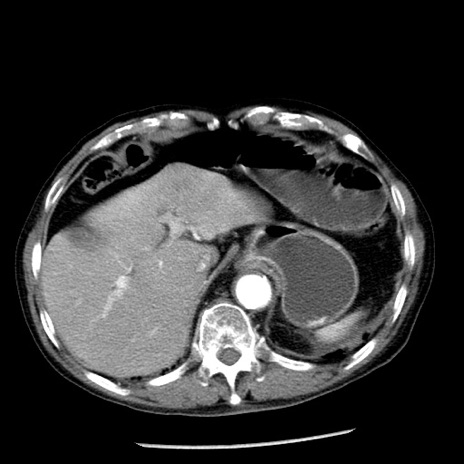

症例26(横断像)

【症例】80歳代男性

【主訴】嘔吐

【現病歴】昨晩2回嘔吐あり、今朝になっても嘔吐あり。来院。

【既往歴】胃潰瘍

【身体所見】意識清明、BT 37.6℃、BP 166/95mmHg、HR 100bpm、SpO2 97%、腹部:平坦・軟、腸蠕動音聴取良好、圧痛なし。

【データ】WBC 21900、CRP 1.46